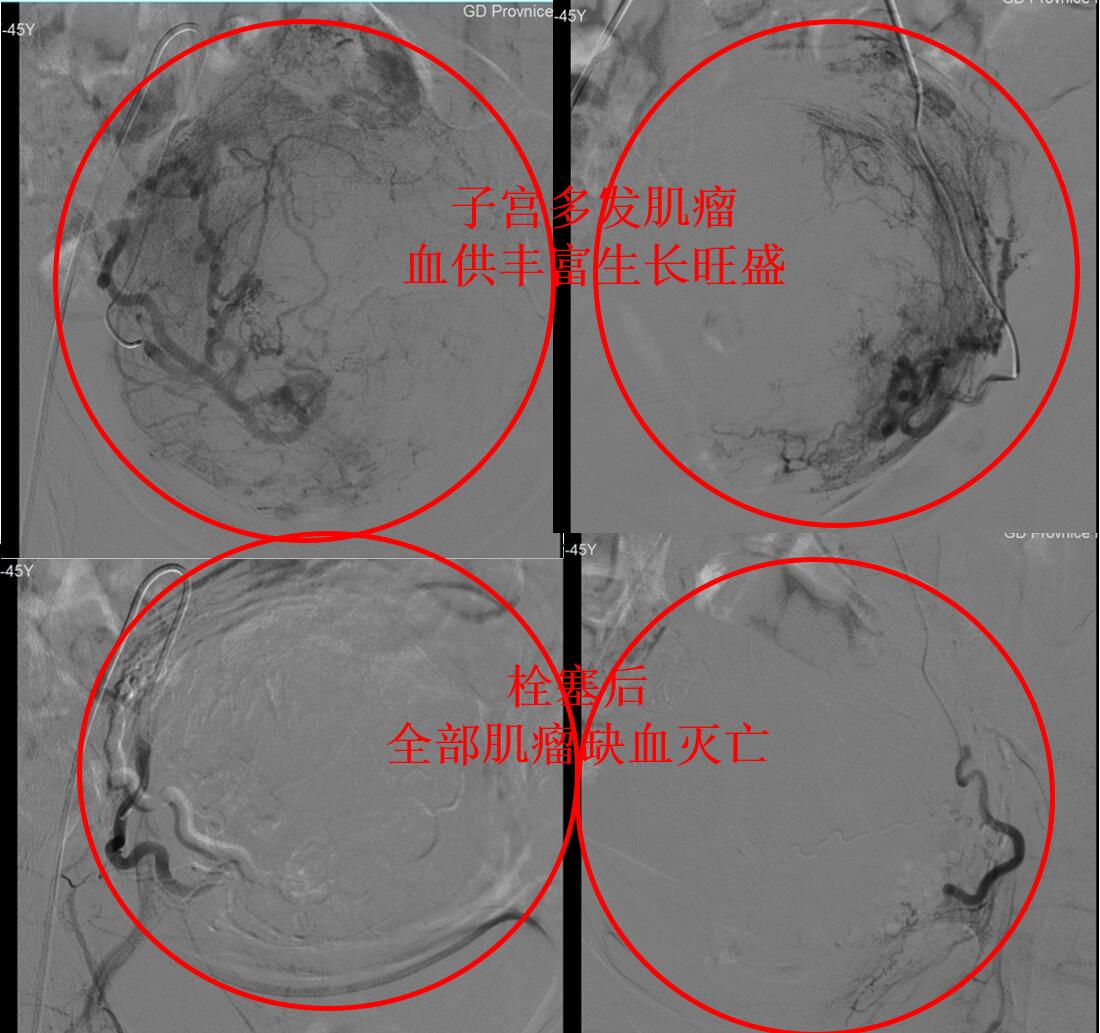

经大腿打针超选择栓塞子宫肌瘤的供血血管(如下图),随后肌瘤缺血死掉排出或者吸收缩小。